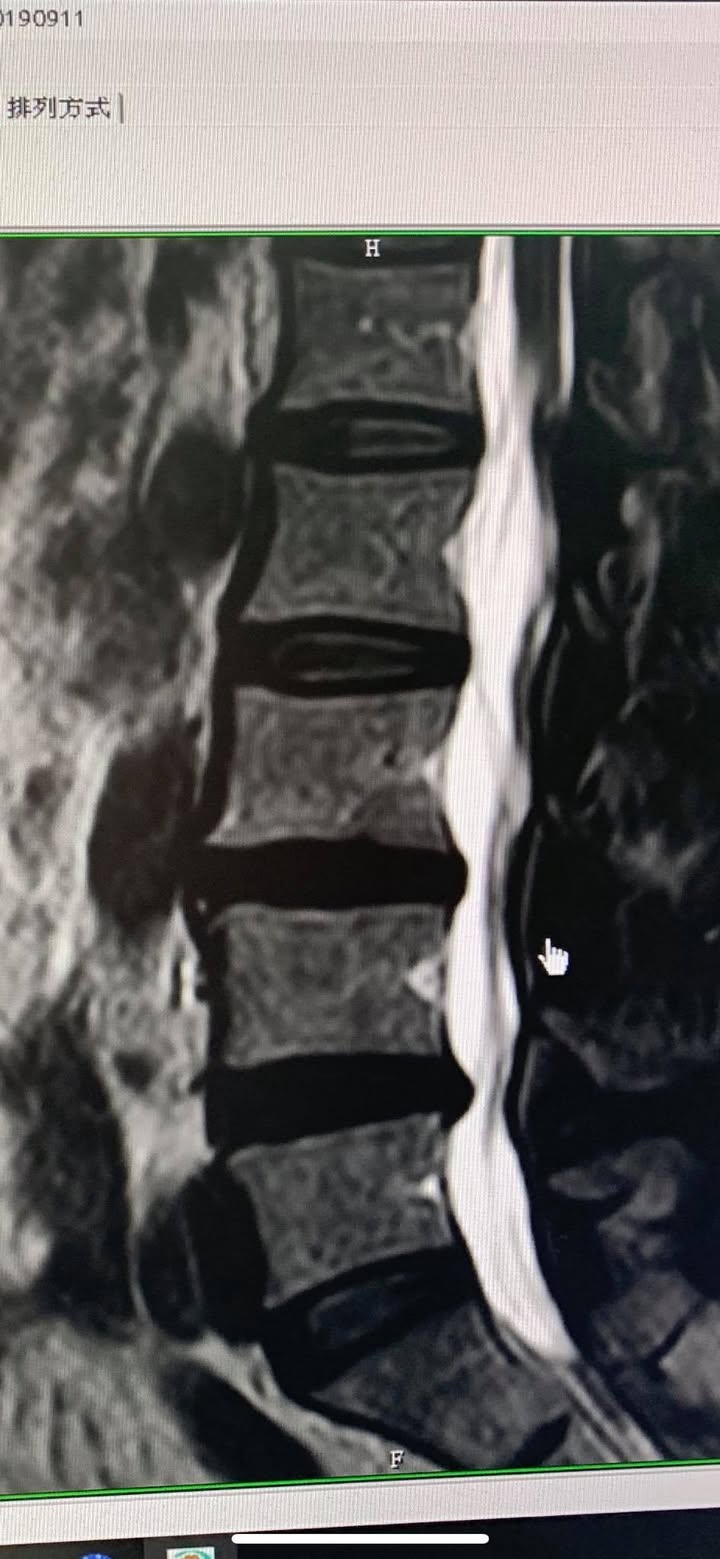

第四椎間盤突出壓迫神經根與硬膜囊